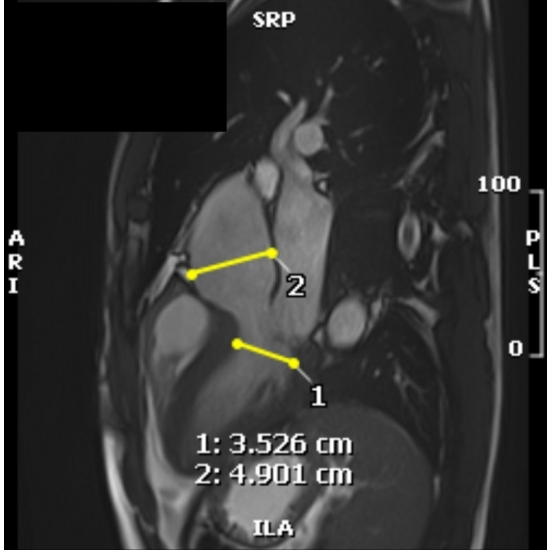

Screening electrocardiogram revealed atrial fibrillation with a ventricular rate of 94 beats per minute Case Photo #1 , and a three-day Holter monitor resulted in a 100 percent atrial fibrillation burden with an average heart rate of 110 beats per minute Case Photo #2 . A transthoracic echocardiogram showed severe aortic sinus and ascending aorta dilation to a maximum diameter of 5.10 centimeters (at his age, normal is considered 2.5 centimeters to 3.5 centimeters). It also revealed a mildly dilated left ventricle with normal wall thickness, systolic function, and diastolic function. It showed mild right ventricle dilation with normal systolic function. Mild aortic, mitral, tricuspid, and pulmonic regurgitation was present. The inferior vena cava was mildly dilated. Computerized tomography angiography confirmed the presence of a dilated aortic root with a maximum diameter of 5.30 centimeters at the sinus of Valsalva Case Photo #3 . On review of imaging records from his prior school, he received a screening transthoracic echocardiogram as a part of his pre-participation evaluation, which revealed the initial aortic root dilation. Subsequent workup at his previous school with a CT angiogram revealed a maximum diameter of the aortic root of 5.10 centimeters one year ago. Cardiac magnetic resonance imaging with and without intravenous contrast reiterated all findings as noted above and showed that the aortic size was normal above the level of the mid-ascending aorta Case Photo #4 . Computerized tomography coronary angiography was done about two months after the initial imaging listed above, which revealed no coronary artery atherosclerosis and revealed a maximum aortic root dilation of 5.60 centimeters Case Photo #5 . Based on these results, he had an aortic root z-score of 7.90 (normal variance is negative 2 to positive 2). (1-2)